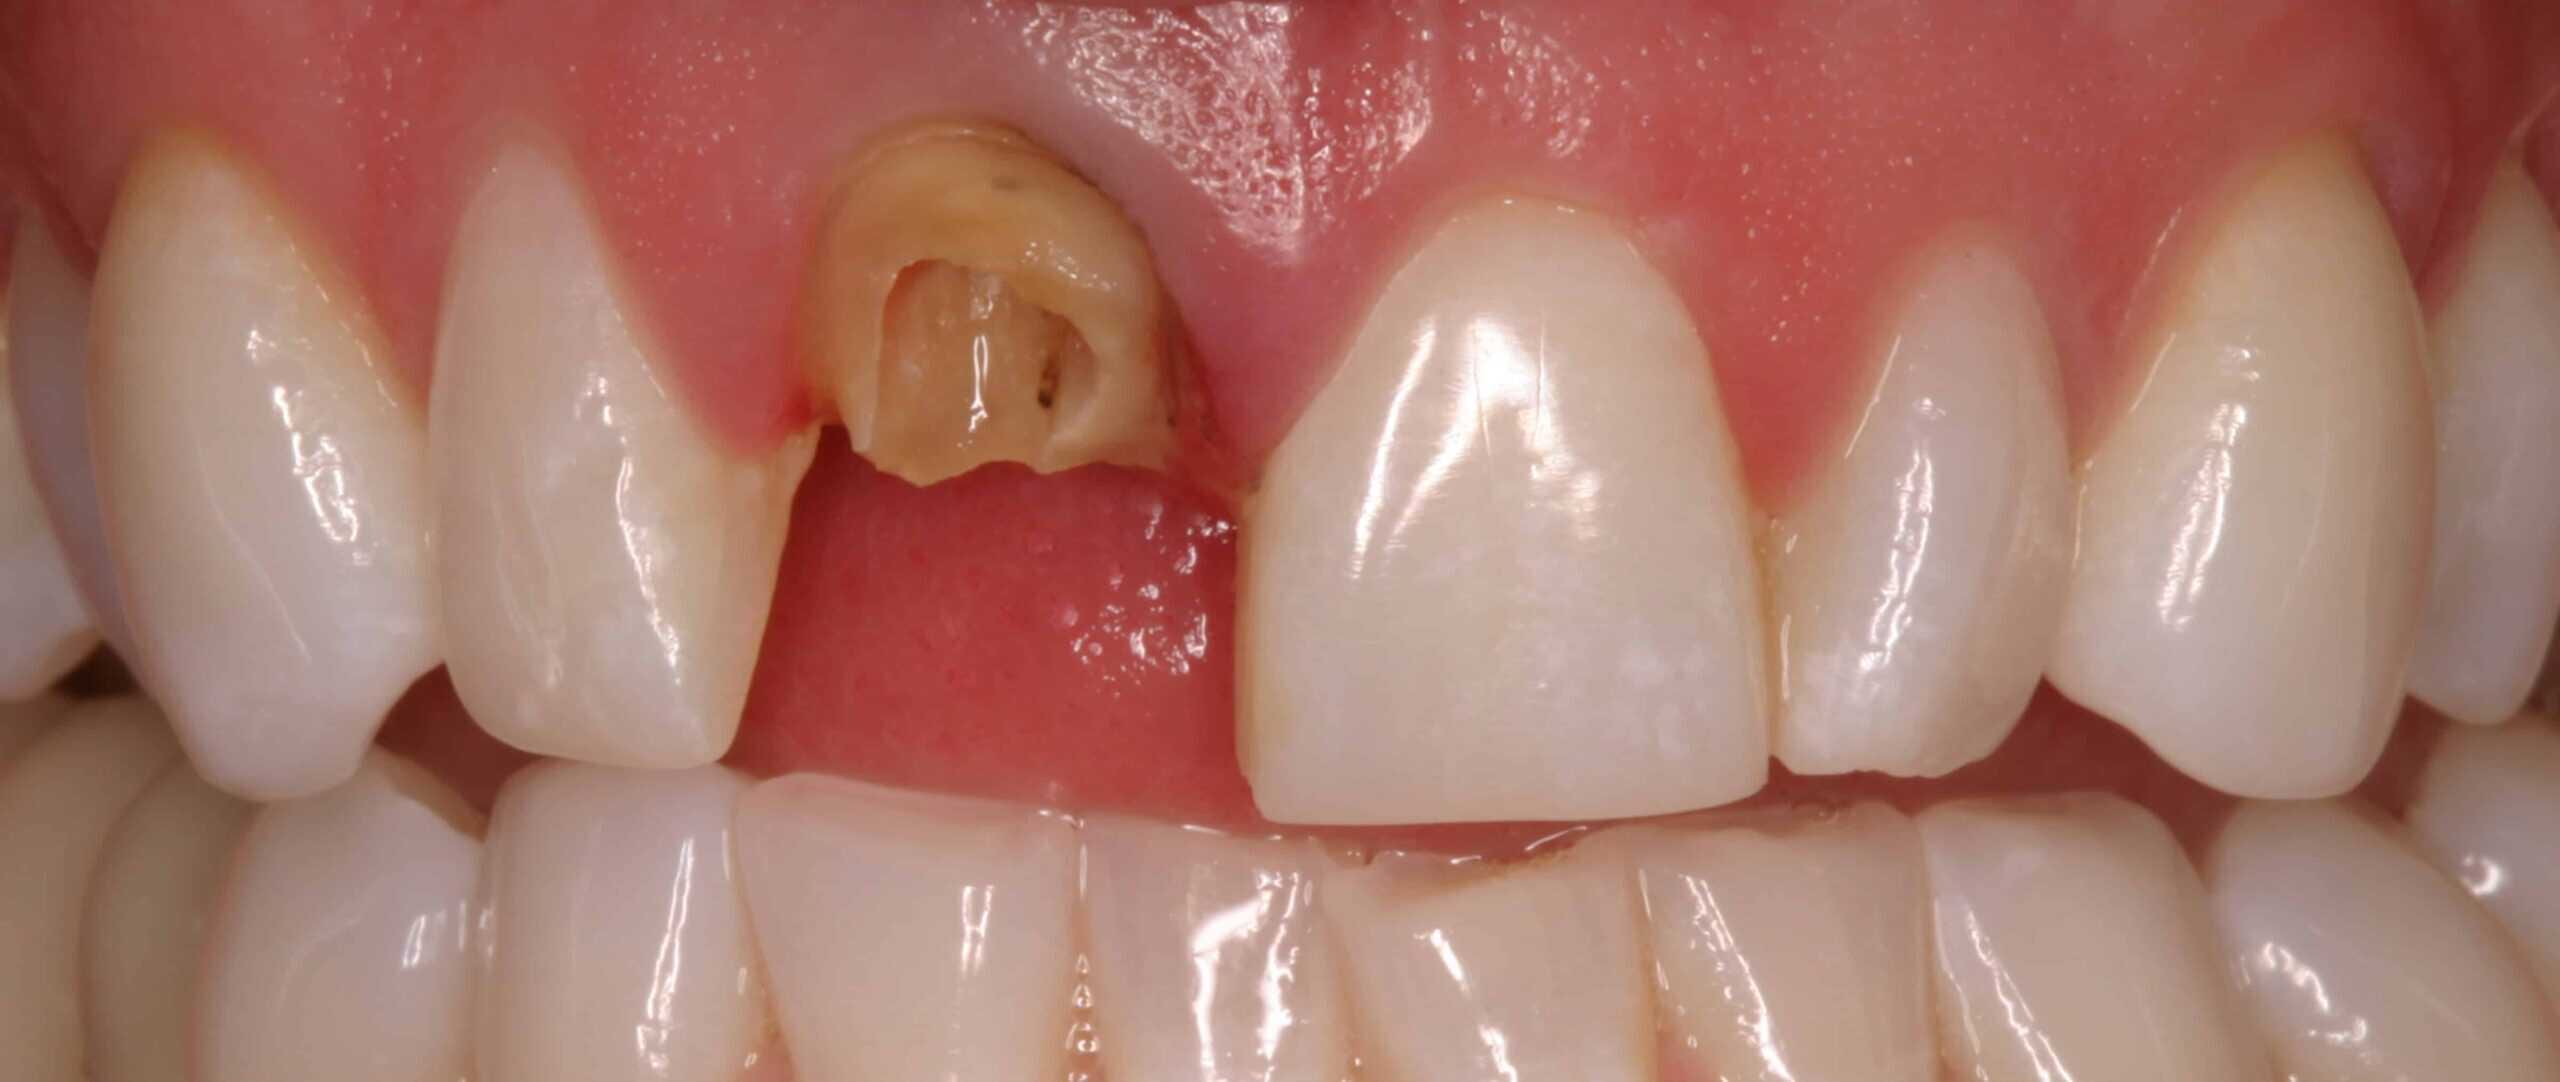

Before:Â Fractured/failed heavily treated upper right central incisor (tooth #8). The root is non-restorable and requires removal. The treatment of choice is a single implant supported restoration.